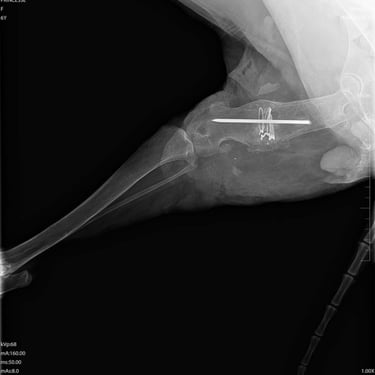

Nous voulions la prendre en charge après sa chirurgie, la mettre en pension et la préparer au départ pour qu'elle ait la chance de vivre quelques années heureuse dans une famille, mais la vie en a décidé autrement, malheureusement, et elle est décédée sur la table d'opération...